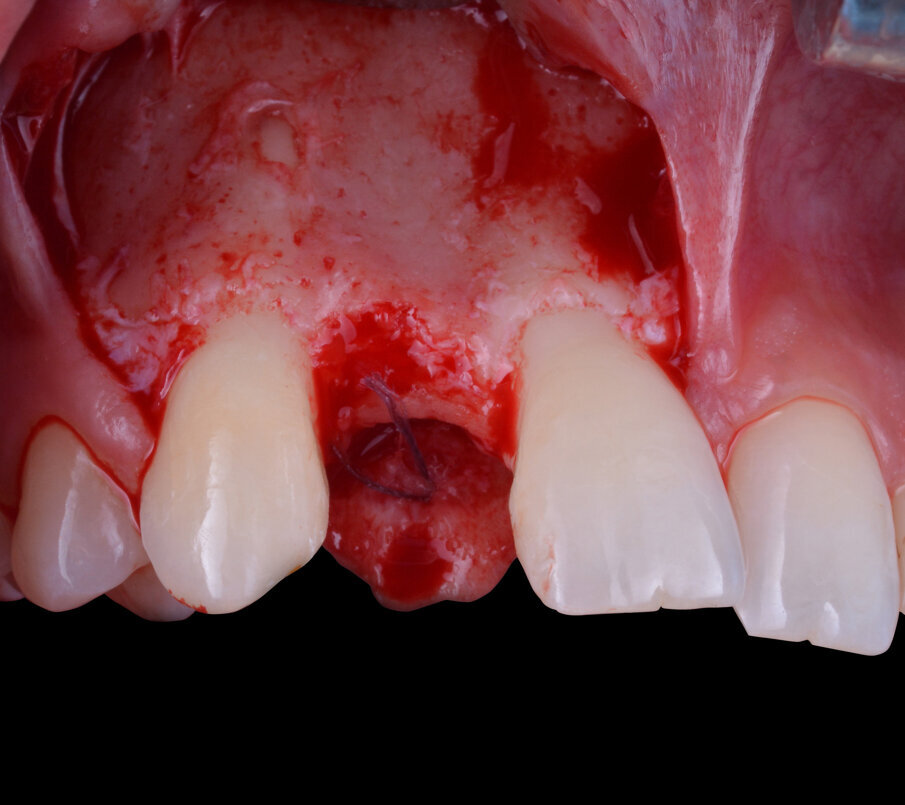

La fase chirurgica successiva consiste nella scheletrizzazione del sito da trattare così da rendere visivamente evidente quanto già evinto dallo studio preliminare, ovvero una moderata carenza ossea della regione vestibolare del processo alveolare (Fig. 5). La scelta della sistematica implantare da utilizzare ricade sull’impianto endo-osseo “Nobel Biocare Replace Conical Connection”. La strumentazione osteotomica iniziale viene eseguita sotto abbondante irrigazione di acqua fisiologica sterile refrigerata e, dopo una accurata preparazione con una fresa inziale lanceolata, una fresa del diametro di 2,0 mm e un’ultima del diametro di 3,5 mm si procede con l’inserimento di un impianto del diametro di 3,5 mm per 11,5 di lunghezza. Con l’avvitamento dell’impianto all’interno del tunnel osteotomico precedentemente ottenuto si raggiunge un torque di inserzione di circa 30 N/cm2, valore in grado di garantire una fisiologica guarigione del sito trattato.

Fig. 5 - Scollamento del lembo a spessore totale.

Fig. 6 - Impianto endo-osseo in situ e dettaglio della fenestrazione vestibolare.